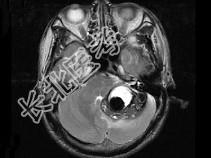

- 单项选择题男,45岁, 反复呕吐近1个月,加重5天, 根据所提供图像,最可能的诊断是 ( )

A、海绵状血管瘤

B、静脉血管畸形

C、脑出血

D、动静脉畸形

E、小脑胶质瘤并出血